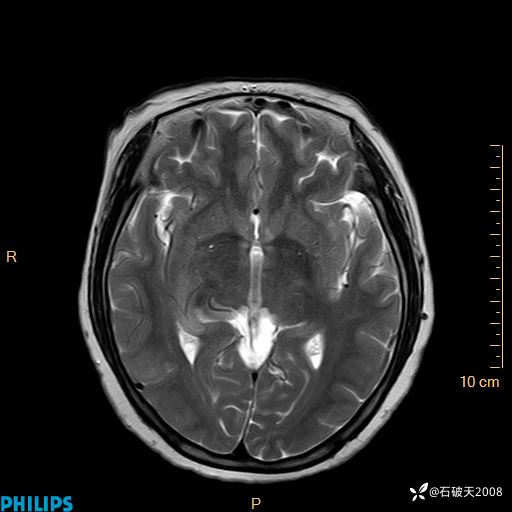

颅内占位,影像征象不是很丰富,有病理

hyy838 推荐女 62岁 主 诉:头晕12小时,加重1小时。

现病史:患者于12小时前无明显诱因出现头晕,呈持续性,无天旋地转及行走不稳,伴恶心、呕吐,呕吐共5次,呕吐物为胃内容物(具体性质不详),无胸闷、胸痛、心慌,无腹痛、腹泻,无咳嗽、咳痰,无发热、意识不清、肢体抽搐及大小便失禁等,1小时前患者上述症状加重,未诊疗,为求进一步治疗急自行来我院,门诊以“头晕待查”为诊断收入我科,发病来,神志清,精神差,饮食、睡眠差,大小便正常,体重未见明显下降。

FILAR